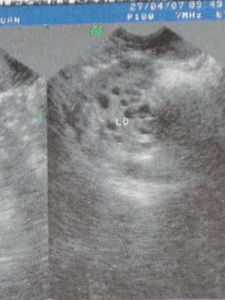

多囊卵巢患者多因不孕問題到醫院就診,多囊卵巢是一種免疫功能異常和內分泌失調交織的綜合症。可用西藥進行多囊卵巢治療,也可用中藥治療多囊卵巢,效果不明顯者可用手術進行多囊卵巢切除術。多囊卵巢在臨床中比較常見,20—40歲的女性多發生多囊卵巢。B超對多囊卵巢的診斷比較準確。

二、B超檢查:雙側的卵巢一般是呈對稱性的,在卵巢內會發現有多個小囊,大小不現,主要是分布是卵巢皮質的周邊。